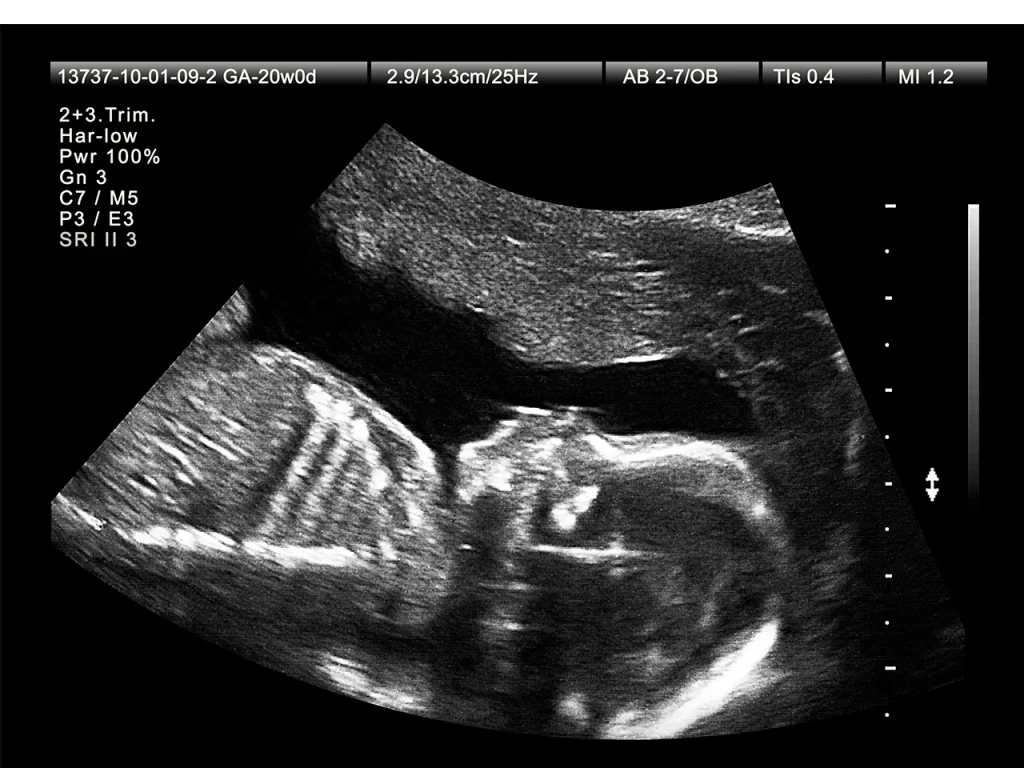

Detaylı ultrason, hamileliğin ikinci trimesterinde yapılan kapsamlı bir anomali taraması olup bebeğin organ gelişimini ve olası doğumsal anomalileri inceleyen bir ultrasonografidir. Genellikle 18-22. gebelik haftaları ...